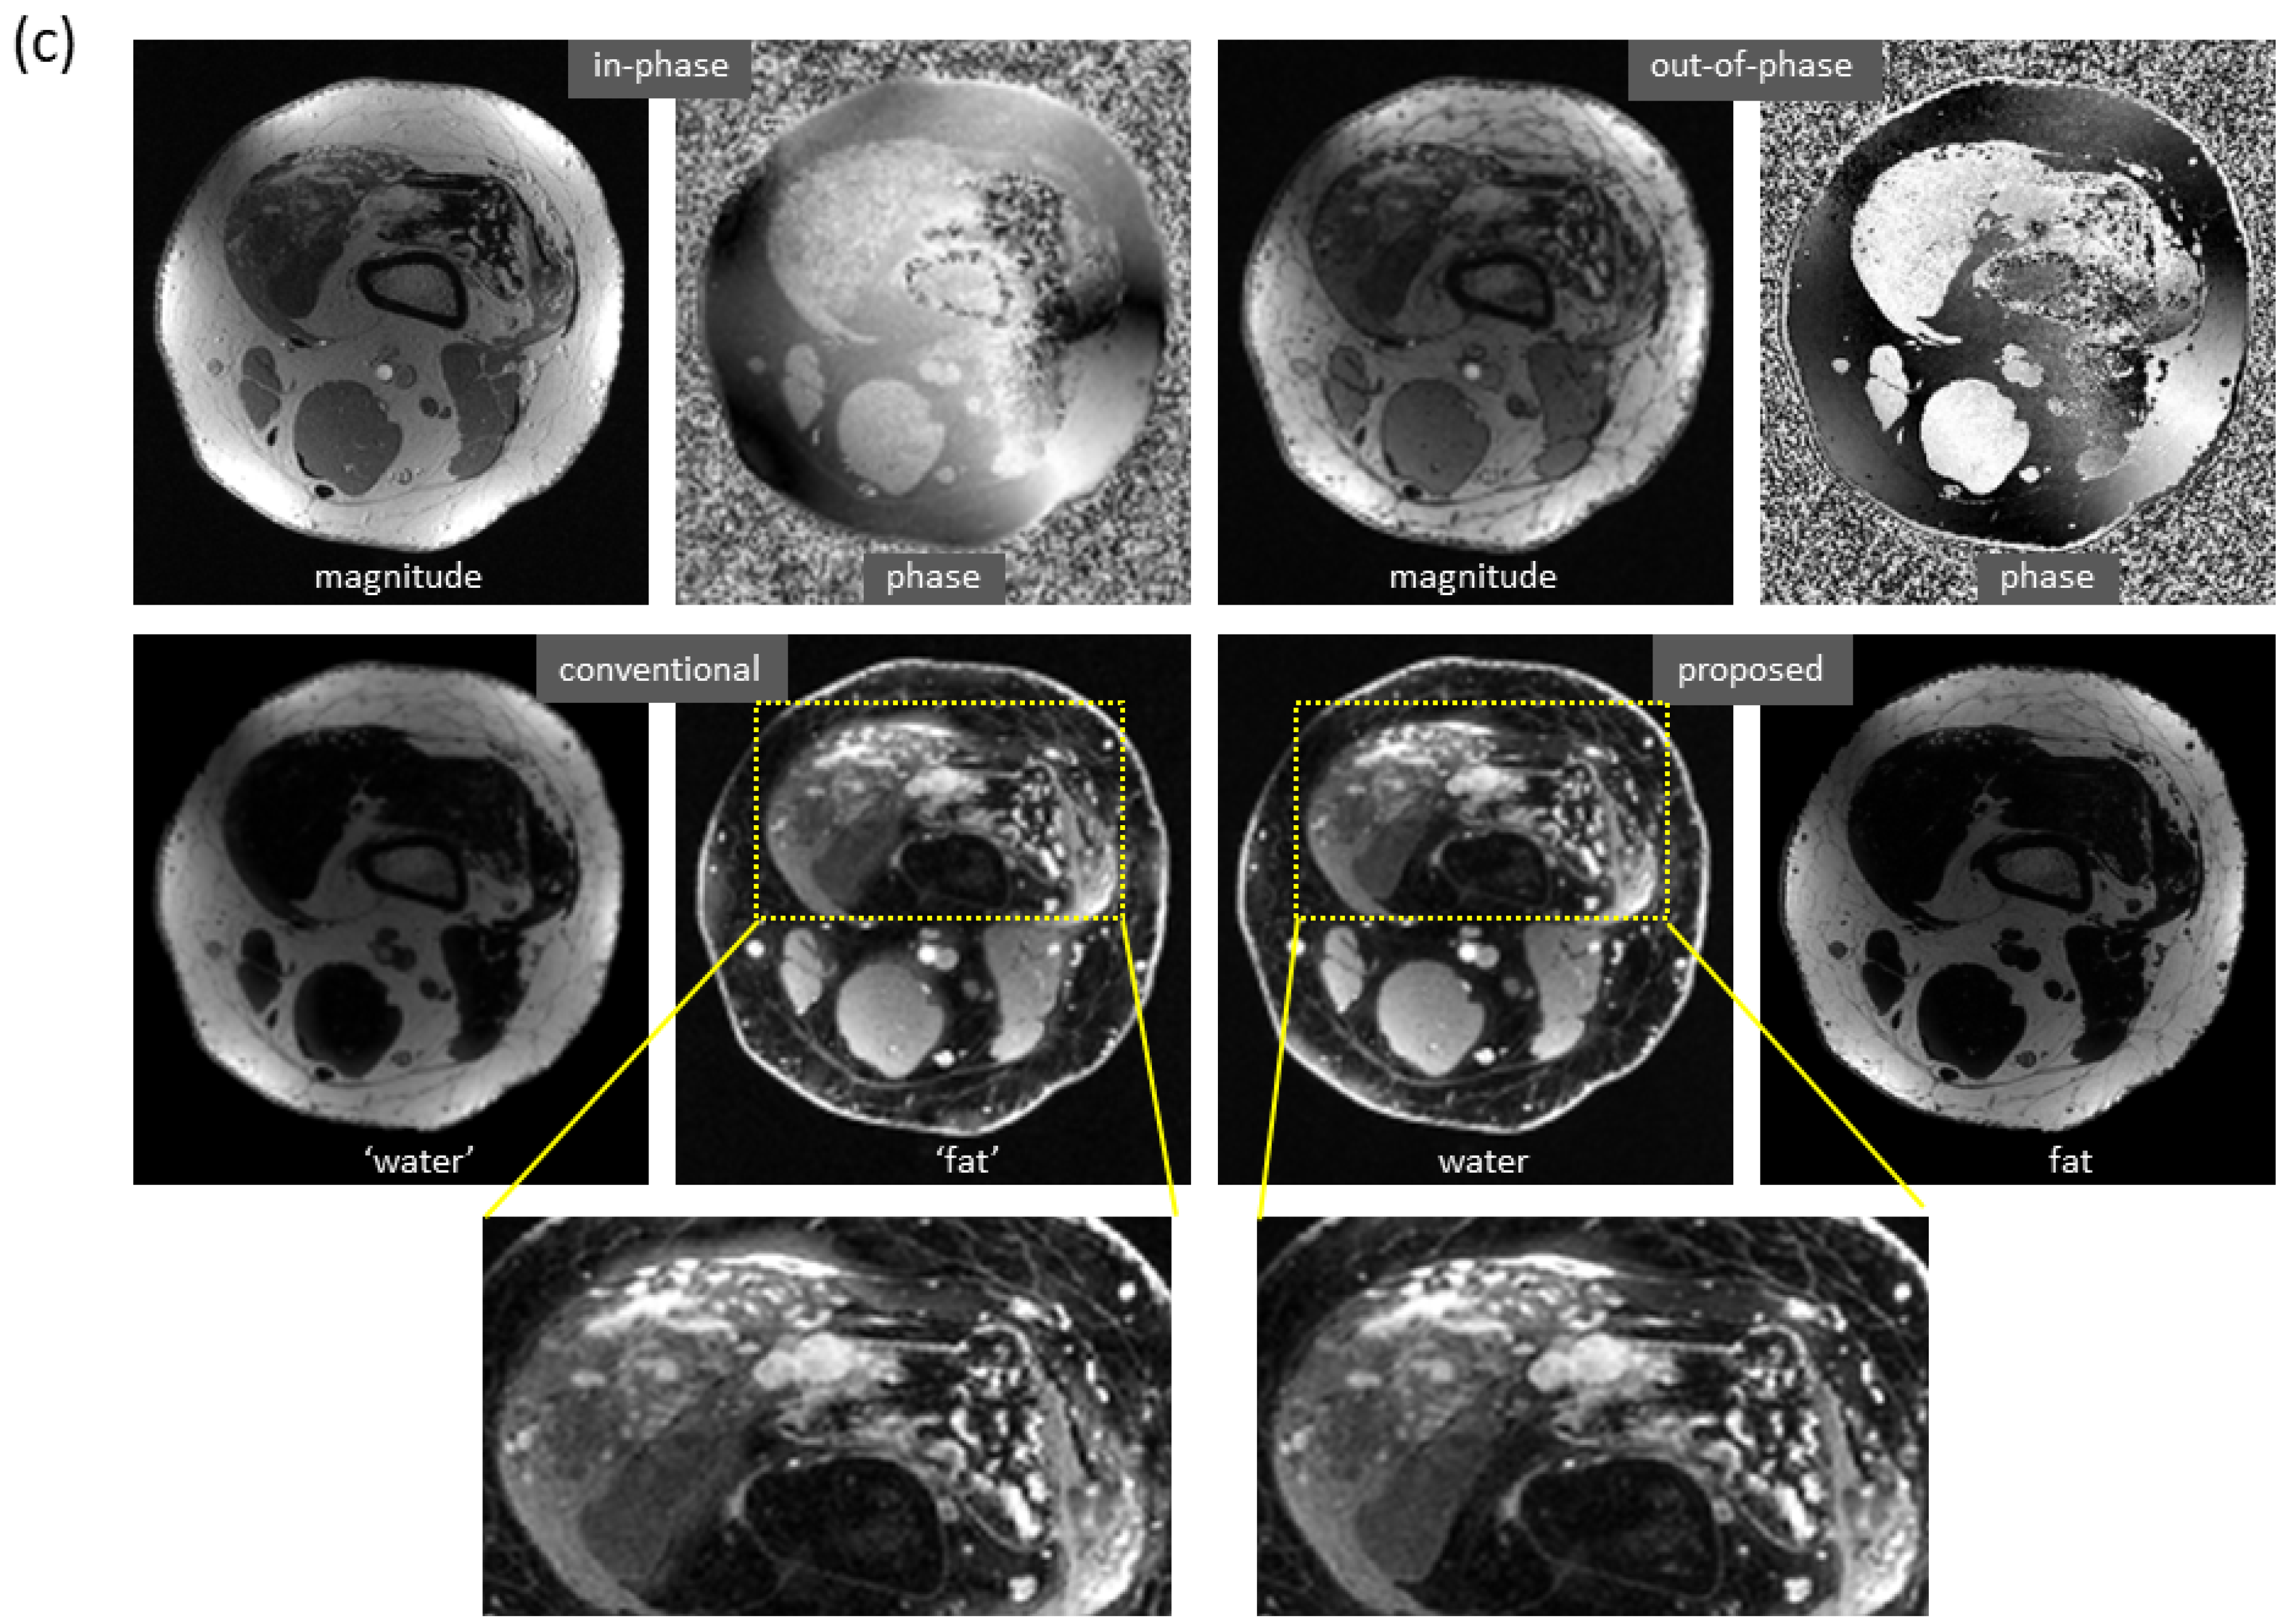

More examples with severe local water/fat swaps as well as global water/fat swaps are shown in Figure 5. In an ankle examination (Figure 5a), as the slices moved farther from isocenter, progressively severe water/fat swaps occurred in the peripheral region of reference images; the water/fat swaps were corrected in the predicted images. In a foot examination (Figure 5b), severe water/fat swaps appeared in the reference images (the dashed arrow pointed to an accessory ossicle with edema, and a local swap appeared in its marrow); the predicted images only had a few smaller swaps. In a knee study (Figure 5c), global water/fat swaps occurred, which in fact was not uncommon in conventional water–fat separation. Using the proposed method, global water/fat swaps were eliminated, and a slightly improved spatial resolution was observed, which can be attributed to the use of convolution for upsampling (expected to outperform conventional upsampling processing).

Figure 5. Marked correction of severe water/fat swaps. (a) In an examination of the ankle, progressively severe water/fat swaps occurred in the reference images as they moved farther from isocenter (every ninth slice is shown). In the predicted images, the water/fat swaps were completely corrected. (b) In an examination of the foot, severe water/fat swaps appeared in the peripheral region of the reference images, where the dashed arrow showed an accessory ossicle with marrow edema that also had a local swap in its marrow. The water/fat swaps were substantially compensated in the predicted images, which only had smaller regions of swaps (solid arrows). (c) Global water/fat swaps, which occurred in the reference image, were corrected using the proposed deep learning method. An improved spatial resolution was observed in the predicted image.